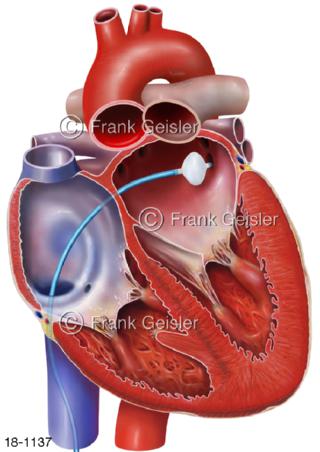

18-1137 Katheterablation, Kryotherapie Kältetherapie

18-1138 Herz Vorhofflimmer, VHF-Ablation, Kryotherapie Kryoablation linker Vorhof, Lungenvenen werden isoliert